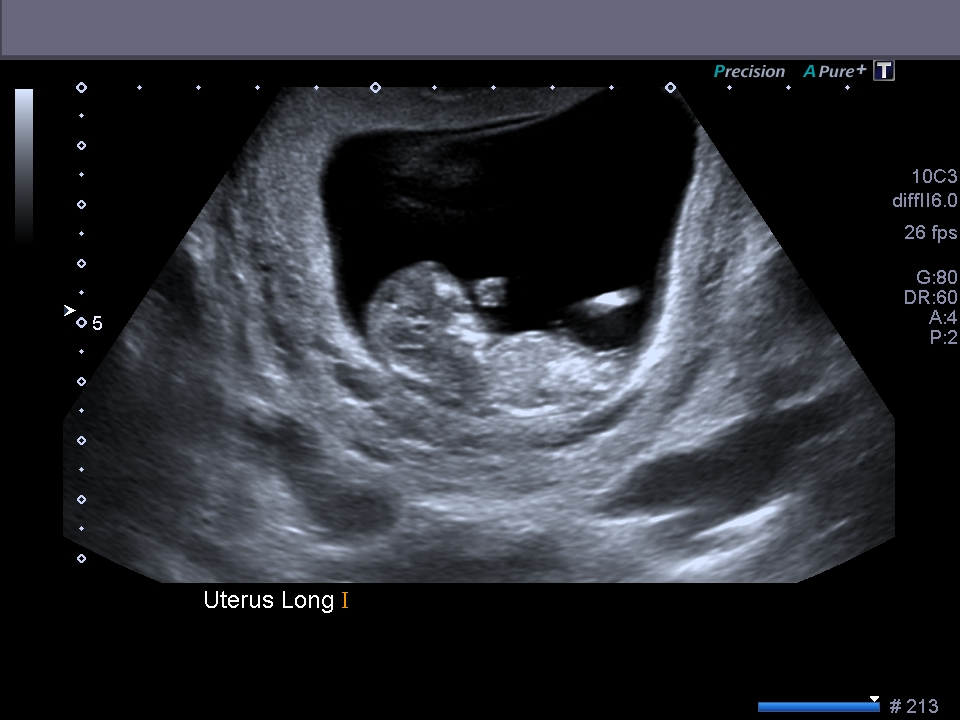

I know these are super early and are not accurate to use but I thought I would post them just for fun and see what everyone thinks :) Thanks xo

Omg, you're already this far?! Time flies so fast haha!! Beautiful baby! Also super early but I say girly because of that forking ;)

Good luck, very early but girlie (my little one had a similar looking fork at 11+6 and have found out it's a girl so fingers crossed for you).